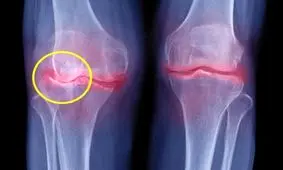

تخریب غضروف مفصلی باعث می شود بافت استخوانی شروع به ساییده شدن کند و مفاصل سفت و دردناک شود.

آرتروز شایعترین نوع از ورم مفاصل است که با افزایش سن وخیمتر میشود. زمان ابتلا به آرتروز ممکن است در جوانی افراد…